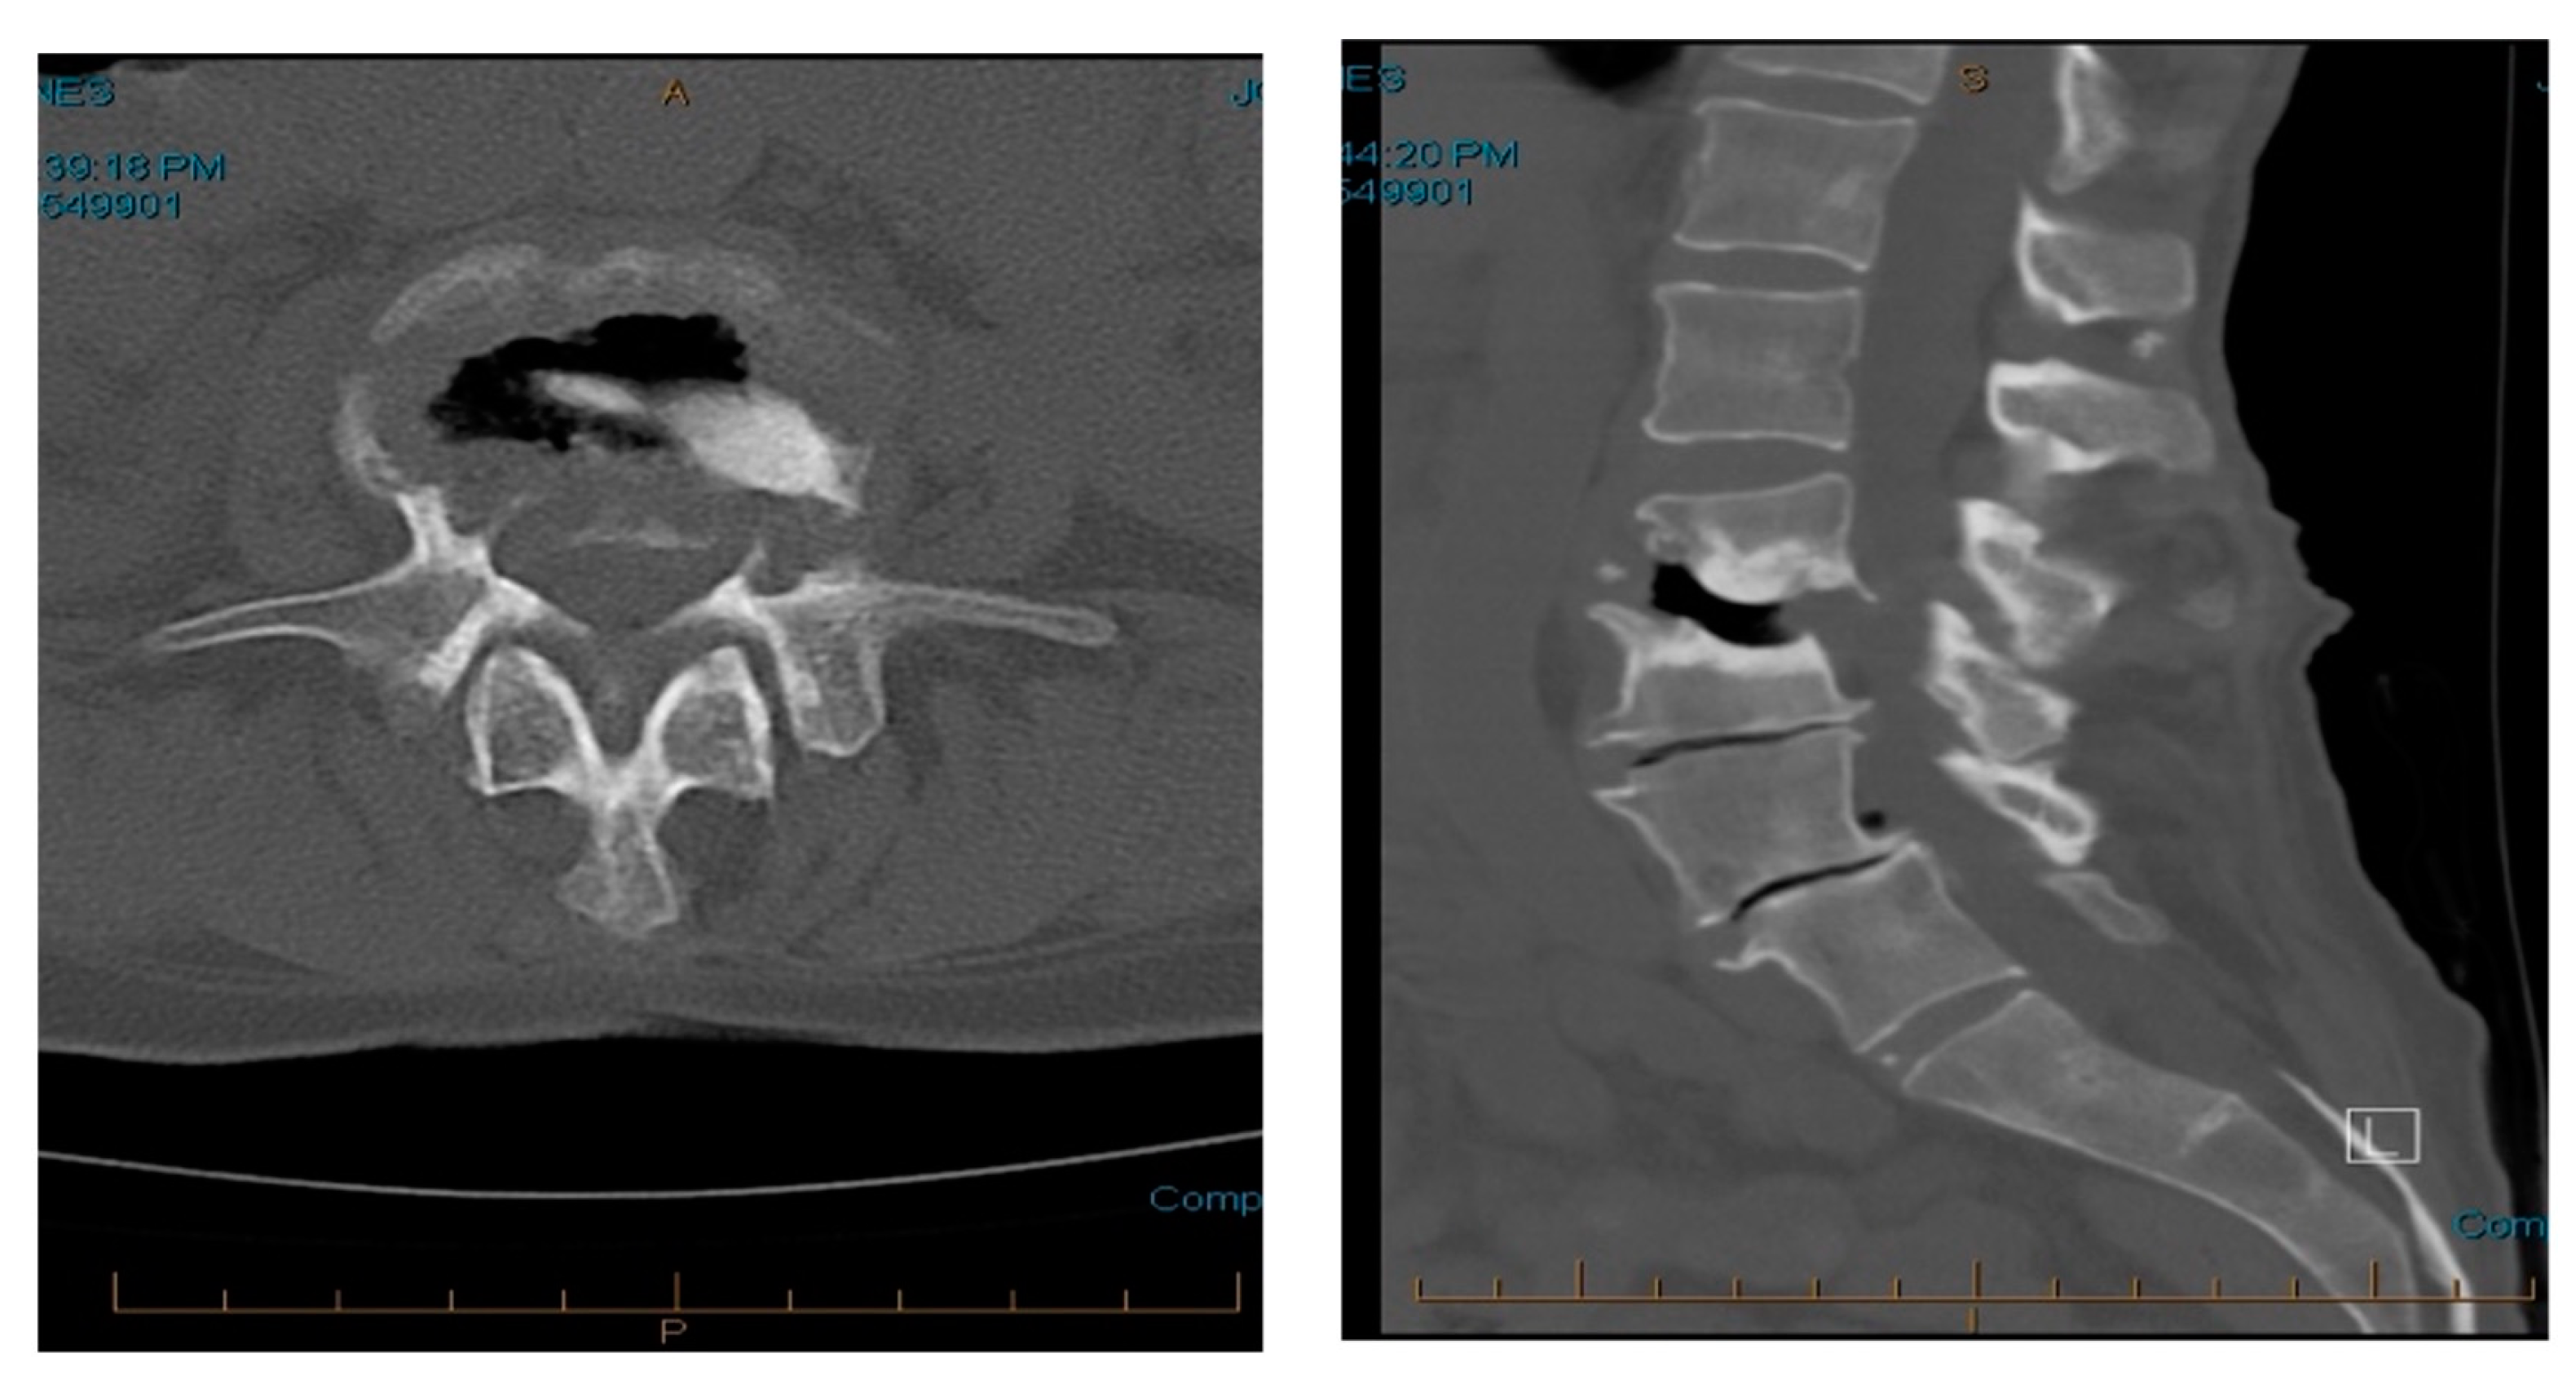

3.2.2. Imaging and Classification

3.2.3. Treatment